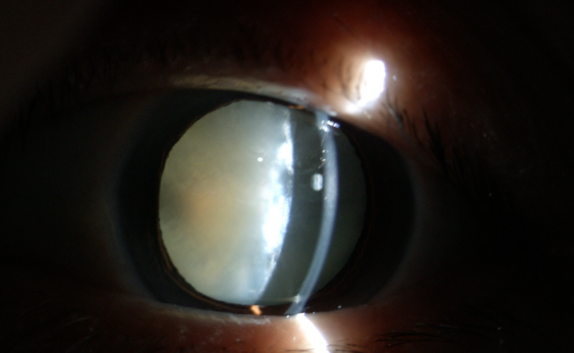

糖尿病為什么更易得白內障

白內障癥狀

糖尿病患者合并白內障盡早手術的原因:白內障發(fā)生后,不但使患者視力產(chǎn)生障礙甚至失明,還直接影響到醫(yī)生對眼底的檢查和治療,因為渾濁的晶狀體阻斷了進出光線。因此,糖友們的白內障手術治療,既能解除視力障礙,還能掃除糖尿病視網(wǎng)膜病變的檢查、治療障礙,所以應盡早手術。